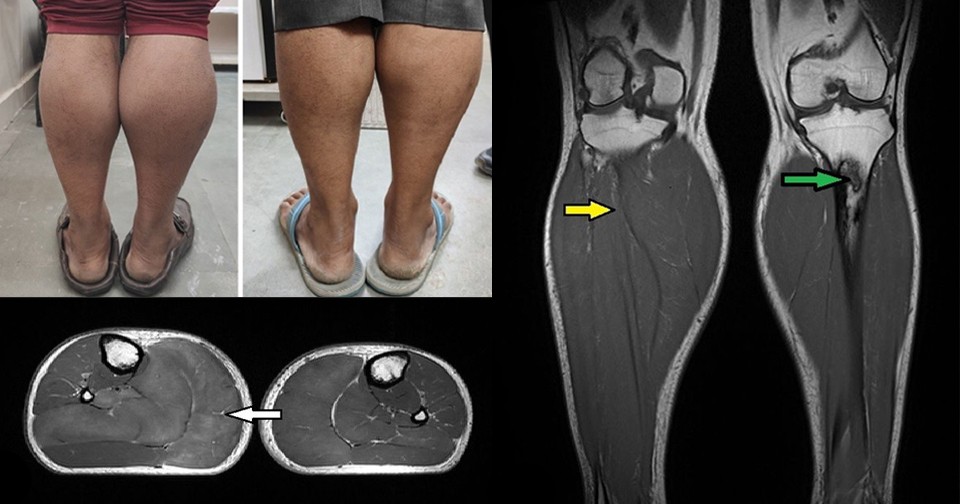

При росте 165 сантиметров мужчина весил 70 килограмм. При поступлении пульс был 69 ударов в минуту, артериальное давление — 116/86 миллиметров ртутного столба. Высшая нервная деятельность была нормальной, обследование сердечно-сосудистой, дыхательной и пищеварительной систем — без особенностей. При осмотре нижних конечностей наблюдались выраженные изолированные отеки обеих икроножных мышц, кожа над ними была плотно натянутой, сухой, огрубевшей и шелушащейся. Наибольший обхват правой голени составлял 43, левой — 38 сантиметров. При проверке коленного рефлекса отмечалась замедленная релаксация мышц.

Осмотр и пальпация щитовидной железы были без особенностей. На УЗИ была видна неоднородная структура с неоднородными (преимущественно гиперэхогенными образованиями) при гладких краях и нормальной васкуляризации железы, что характерно для тиреоидита. ЭКГ показала нормальный синусовый ритм, эхокардиограмма — отсутствие патологических изменений с нормальной фракцией выброса (55 процентов). На МРТ ног визуализировались увеличение объема и отек икроножных и камбаловидных мышц, а также инфаркты большеберцовой кости. На основании данных обследования пациенту поставили диагноз тяжелого гипотиреоза с псевдогипертрофией мышц голеней.